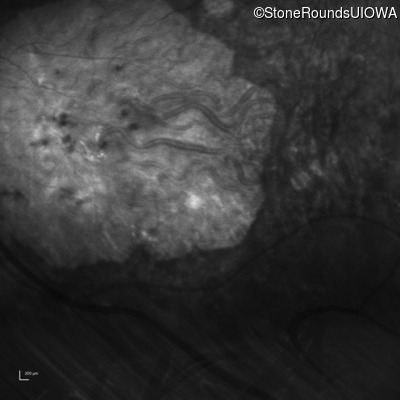

Infrared Fundus Photograph - Right - 20/200 sc

Exemplar